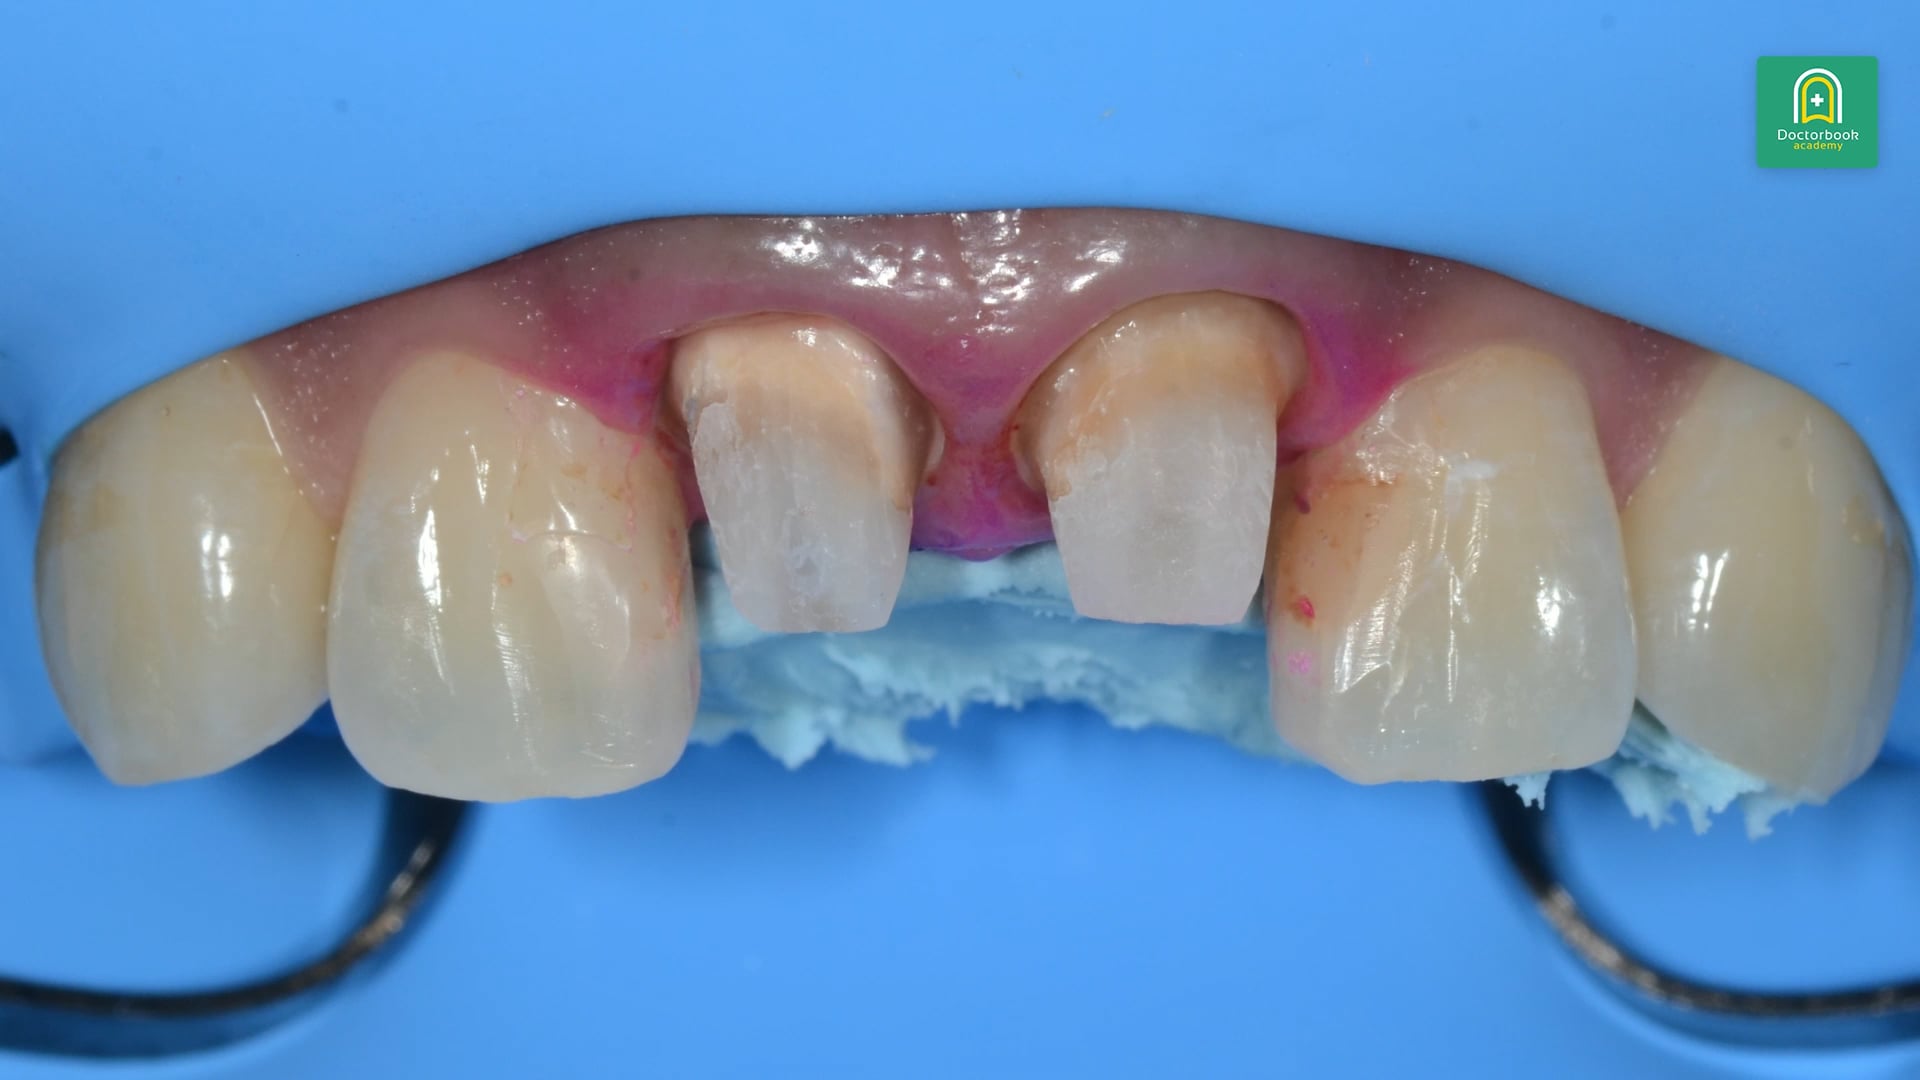

37歳女性、前歯の色が気になるとのことです。

補綴を外し、ダウエルコアも除去していきます。

また、プロビジョナルを装着し歯肉のクリーピングを待ちラバーダム下で補綴物をセットします。

最初に前歯部の歯根近接について着目します。

歯根近接の場合、歯間乳頭ができにくいためです。

実際に今回の症例では支台歯が短く、歯冠が長いため外れるリスクが考えられます。